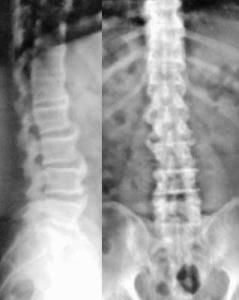

弥漫性特发性骨肥厚(DISH)主要累及脊柱尤其是颈椎,特征是大量而表浅的不规则椎体前和侧缘骨质增生相互间融合形成椎体前广泛肥厚骨块,又称为强直性骨肥厚或Forestier病。本病常见于中老年男性,男女比约为2:1,男女发病率均随着年龄的增长和体重的增加而增高,45岁以前极少罹患本病。[1]